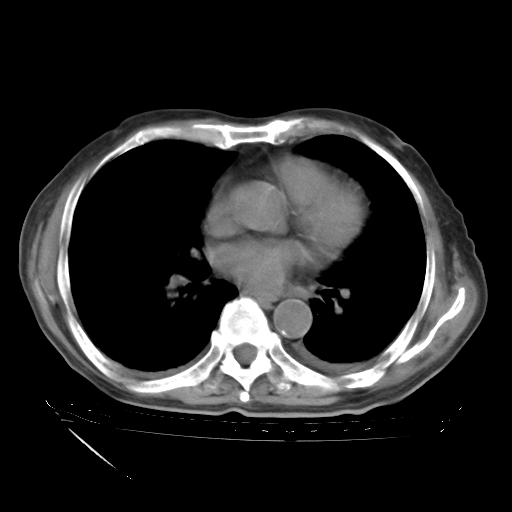

经过24天治疗,岳父的病情基本稳定。生活基本可以自理,可以下床活动。呼吸困难早已消失。体温基本正常。

只是甲强龙用80mg时血小板升到正常,改为60mg后又降到63×10*9/L。

主要治疗甲强龙80mg×14天,60mg×10天;同时抗结核(异烟肼+利福平+乙胺丁醇)。环磷酰胺0.1 tid 10天。

特别感谢胡教授、高管、桃子版主给出关键的治疗建议。桃版把所有肺部影像和全部临床资料请所在医院呼吸科、感染病科、结核科、临床免疫科专家会诊。临床免疫科专家制定了完整的治疗方案。